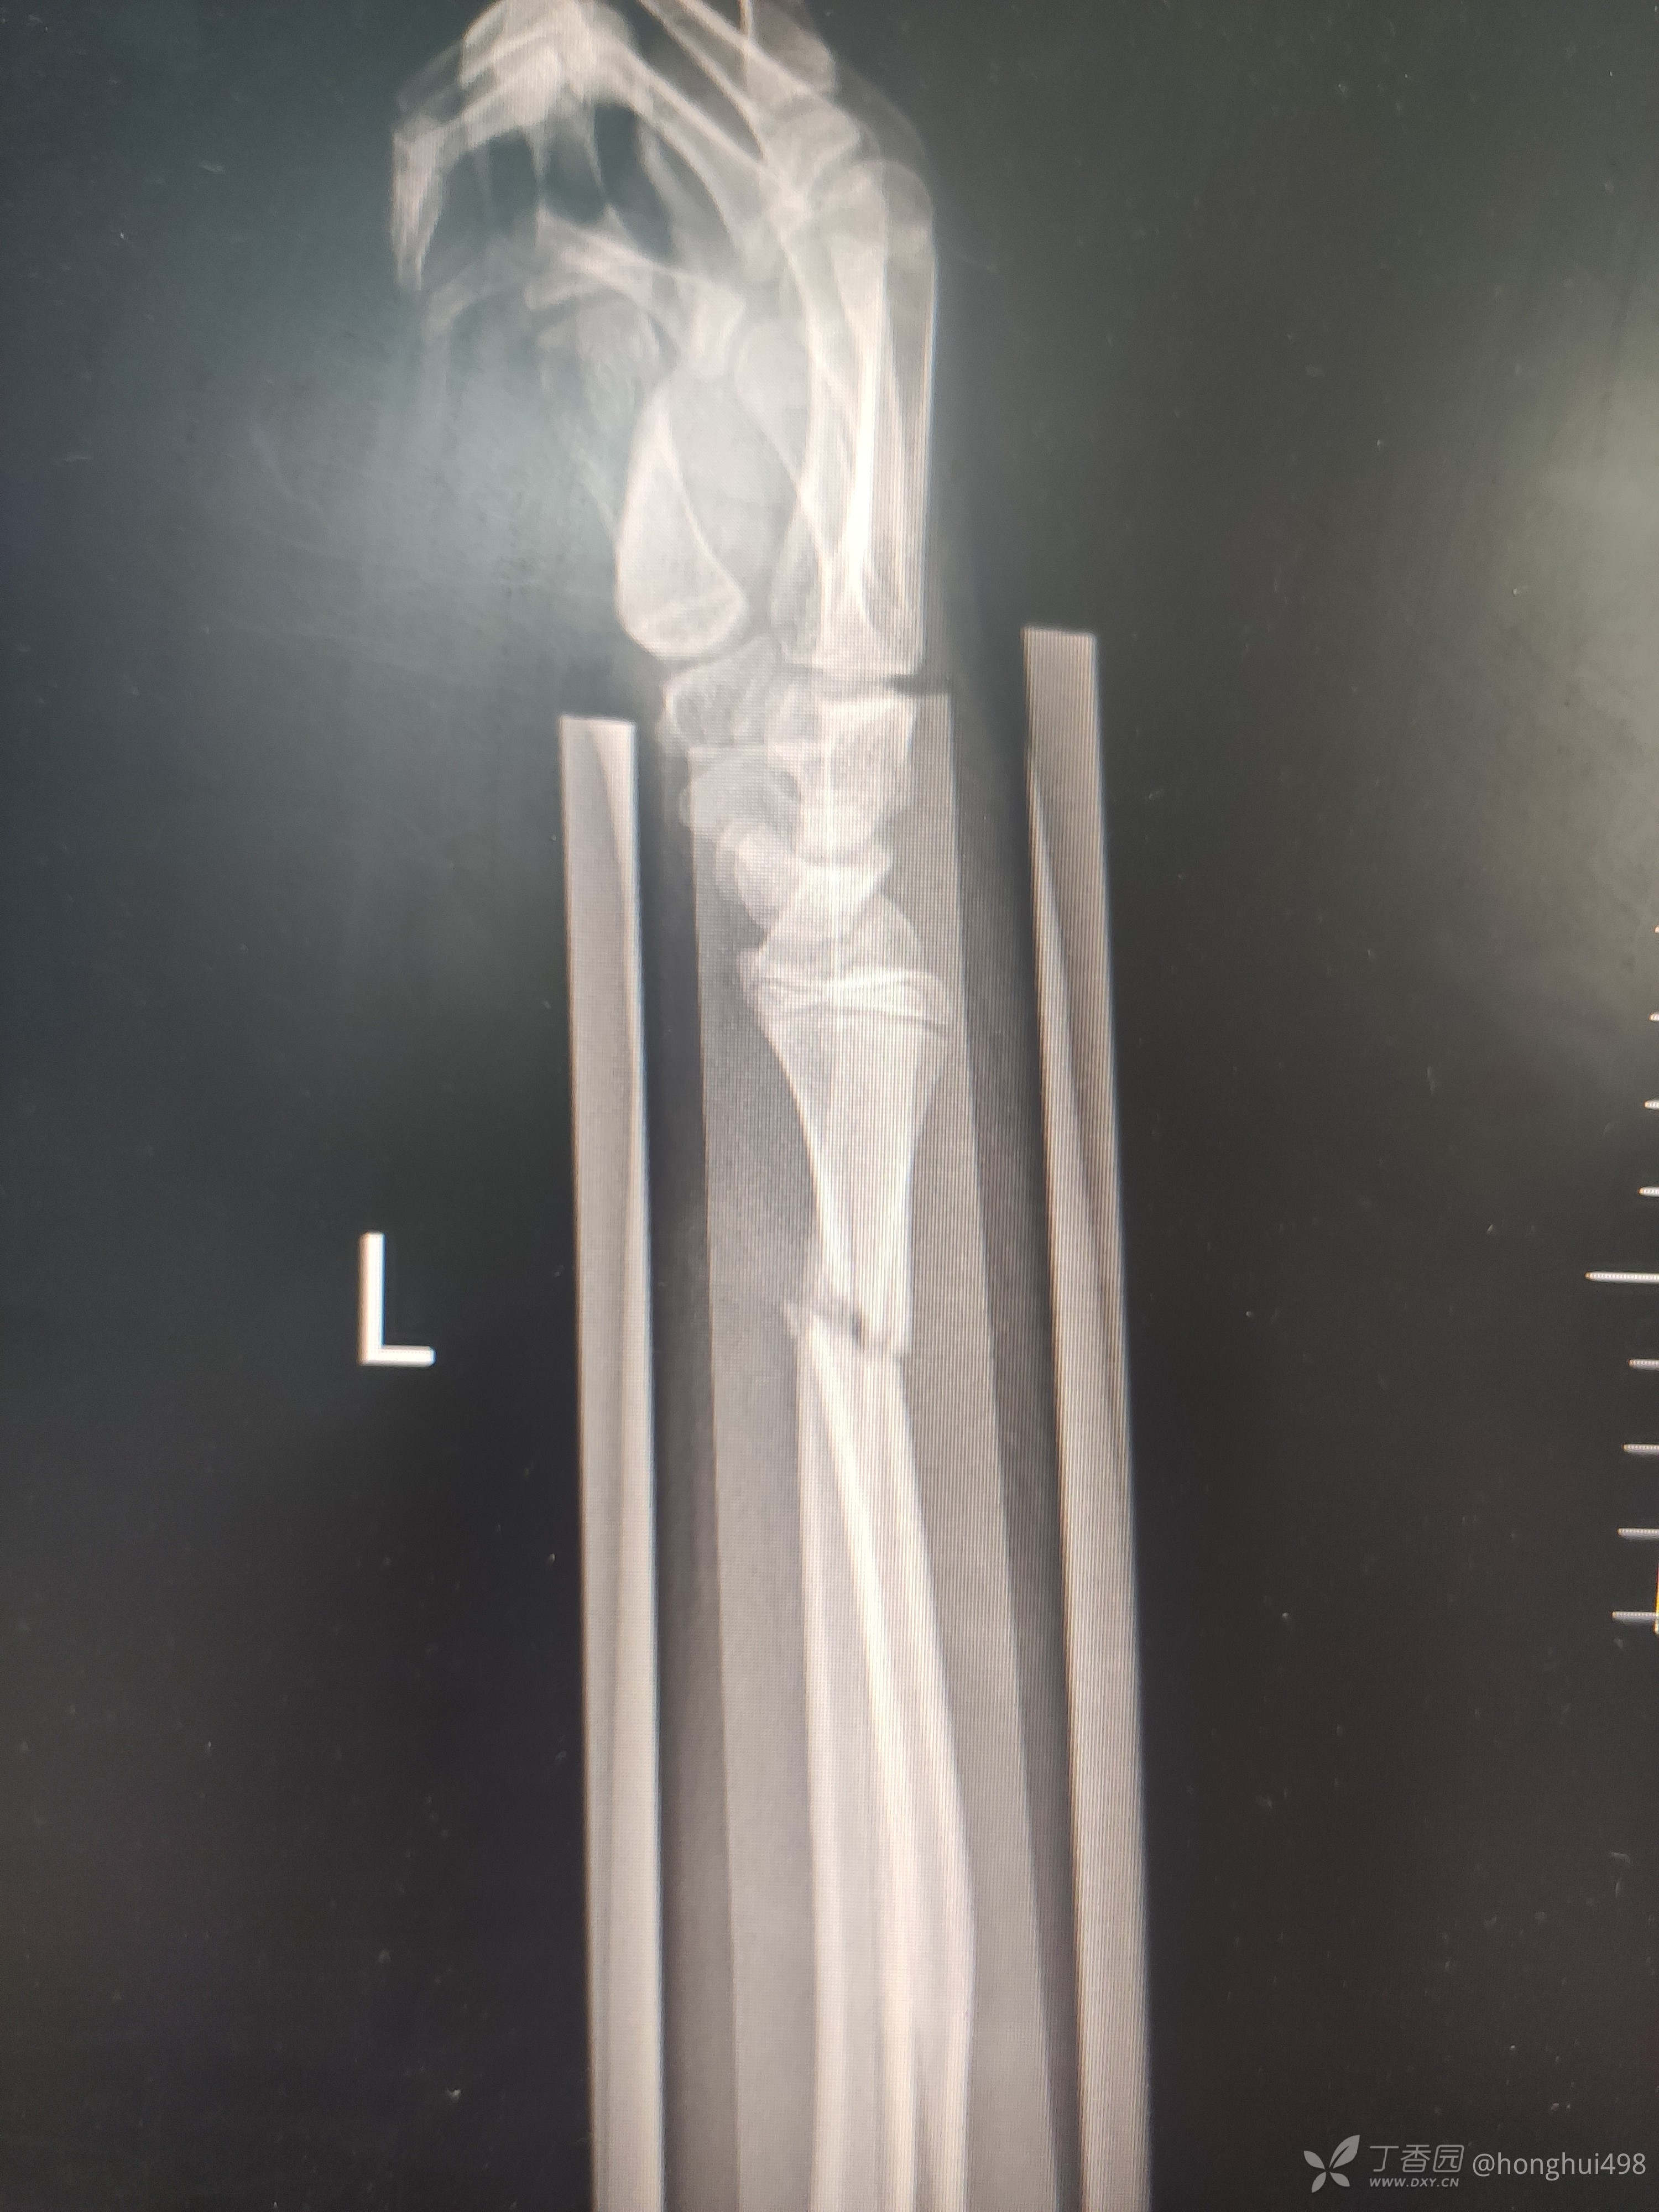

男性,14岁,摔倒致伤,左尺桡骨双骨折,肾病综合征。第一次受伤时手法整复,保守治疗两周后复查再次移位,二次入院手术治疗,术前计划桡骨闭合复位顺行髓内钉固定,术中发现复位不佳,切开复位钢板固定。